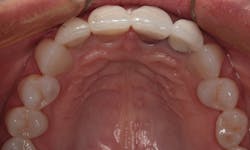

The old crowns were removed; the preparations for the maxillary lateral and central incisors were refined. Veneer preparations were completed for the canines and premolars. In Figure 5, you can see the preparations for four all-ceramic crowns and six veneers. Note that even though there were slight rotations, it was not necessary to break the contacts between the bicuspids and cuspids. This allowed for a more conservative approach that was less invasive. The prepared teeth are shown from the facial view in Figure 6. A new occlusal registration was made using Futar.

Figure 5: Occlusal view of the prepared teeth